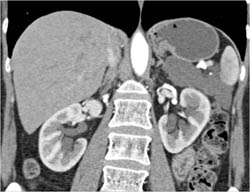

Diagnosis

Lymphangioma